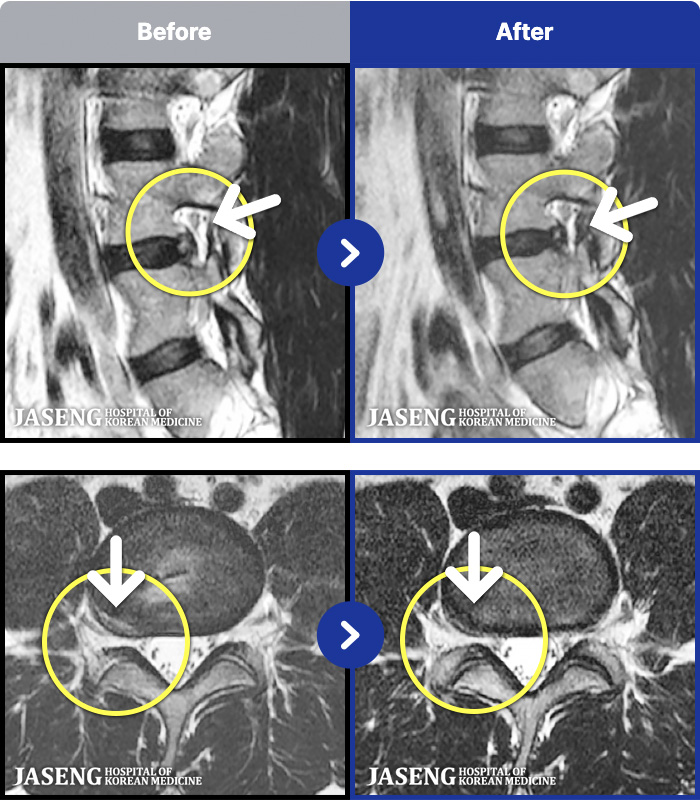

- MRI ġ

MRI ġ

191 MRI ũ ʸ Ȯϼ.

㸮 , , ⸳ Ƹ

[_㸮ũ] 㸮 ٸ ϰ ϻȰ Ұ߽ϴ.

No.191

ȸ 62

2026.03.20